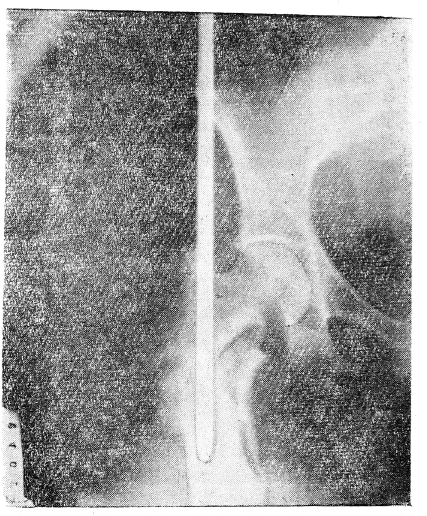

Рис.1. Ренгенограмма левого тазобедренного сустава больного С.

На фоне костей тазобедренного сустава виден небольшой отрезок направляющей спицы. Перелом шейки фиксирован трехлопастным металлическим гвоздем.

Нет сомнения, что во многих случаях, когда консервативными методами не удается сопоставить смещенные отломки и удержать их в правильном положении, наиболее надежным методом является внутрикостная фиксация металлическим стержнем, или штифтом. В ценности этого метода, при строгих показаниях, мы убедились при лечении больных со смещенным переломом шейки бедренной кости, оскольчатым, двойным и открытым переломом диафиза. Причем остеосинтез трехлопастным гвоздем при медиальном переломе шейки бедра на данном этапе следует считать методом выбора. Опыт нашего института подтверждает, что фиксация медиального перелома шейки бедра трехлопастным гвоздем позволяет рано поднимать больных, ставить их на ноги, предупреждая тем самым тяжелые осложнения, как, например, пролежни, „гипостатическая" пневмония. К положительным качествам трехлопастного гвоздя относится то, что при минимальной площади поперечного сечения он обладает чрезвычайно большой прочностью на изгиб. Следовательно, фиксируя отломки и доводя их до степени сколоченности, этот вид остеосинтеза очень незначительно разрушает костную ткань. Что касается винтов, применяемых для этих целей (Я. Н. Родин и др.), то вопросы прочности их подлежат изучению. Применение толстых винтов намного больше разрушает костную ткань, что может иметь отрицательное значение для восстановления кровообращения в головке. Вместе с тем, надо признать, что техника введения и трехлопастного гвоздя требует дальнейшей разработки, так как методика его введения с помощью спицы не всегда обеспечивает успех. Так, известны случаи резкого искривления спицы (С. Е. Кашкаров), которое препятствовало продвижению гвоздя, а также были случаи полного отсечения конца спицы гвоздем (рис. 1).